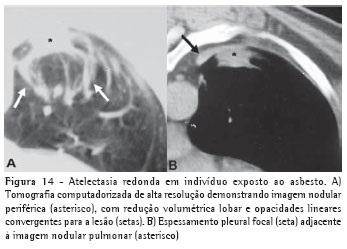

Atelectasia redondaA atelectasia redonda constitui um colapso pulmonar periférico que se apresenta na forma de massa, quase sempre em associação com alterações pleurais. Apesar de poder ocorrer em associação com inflamação pleural, decorrente de cirurgias, infecções ou traumas, a exposição ao asbesto é a sua etiologia mais comum. Na radiografia simples pode ser caracterizada como uma massa pulmonar periférica associada a espessamento pleural e distorção do parênquima pulmonar adjacente.

Entretanto, a TCAR tem maior eficácia diagnóstica (Figura 14), demonstrando opacidade periférica com distorção dos vasos pulmonares ou brônquios na sua periferia e com alteração pleural adjacente.(15)